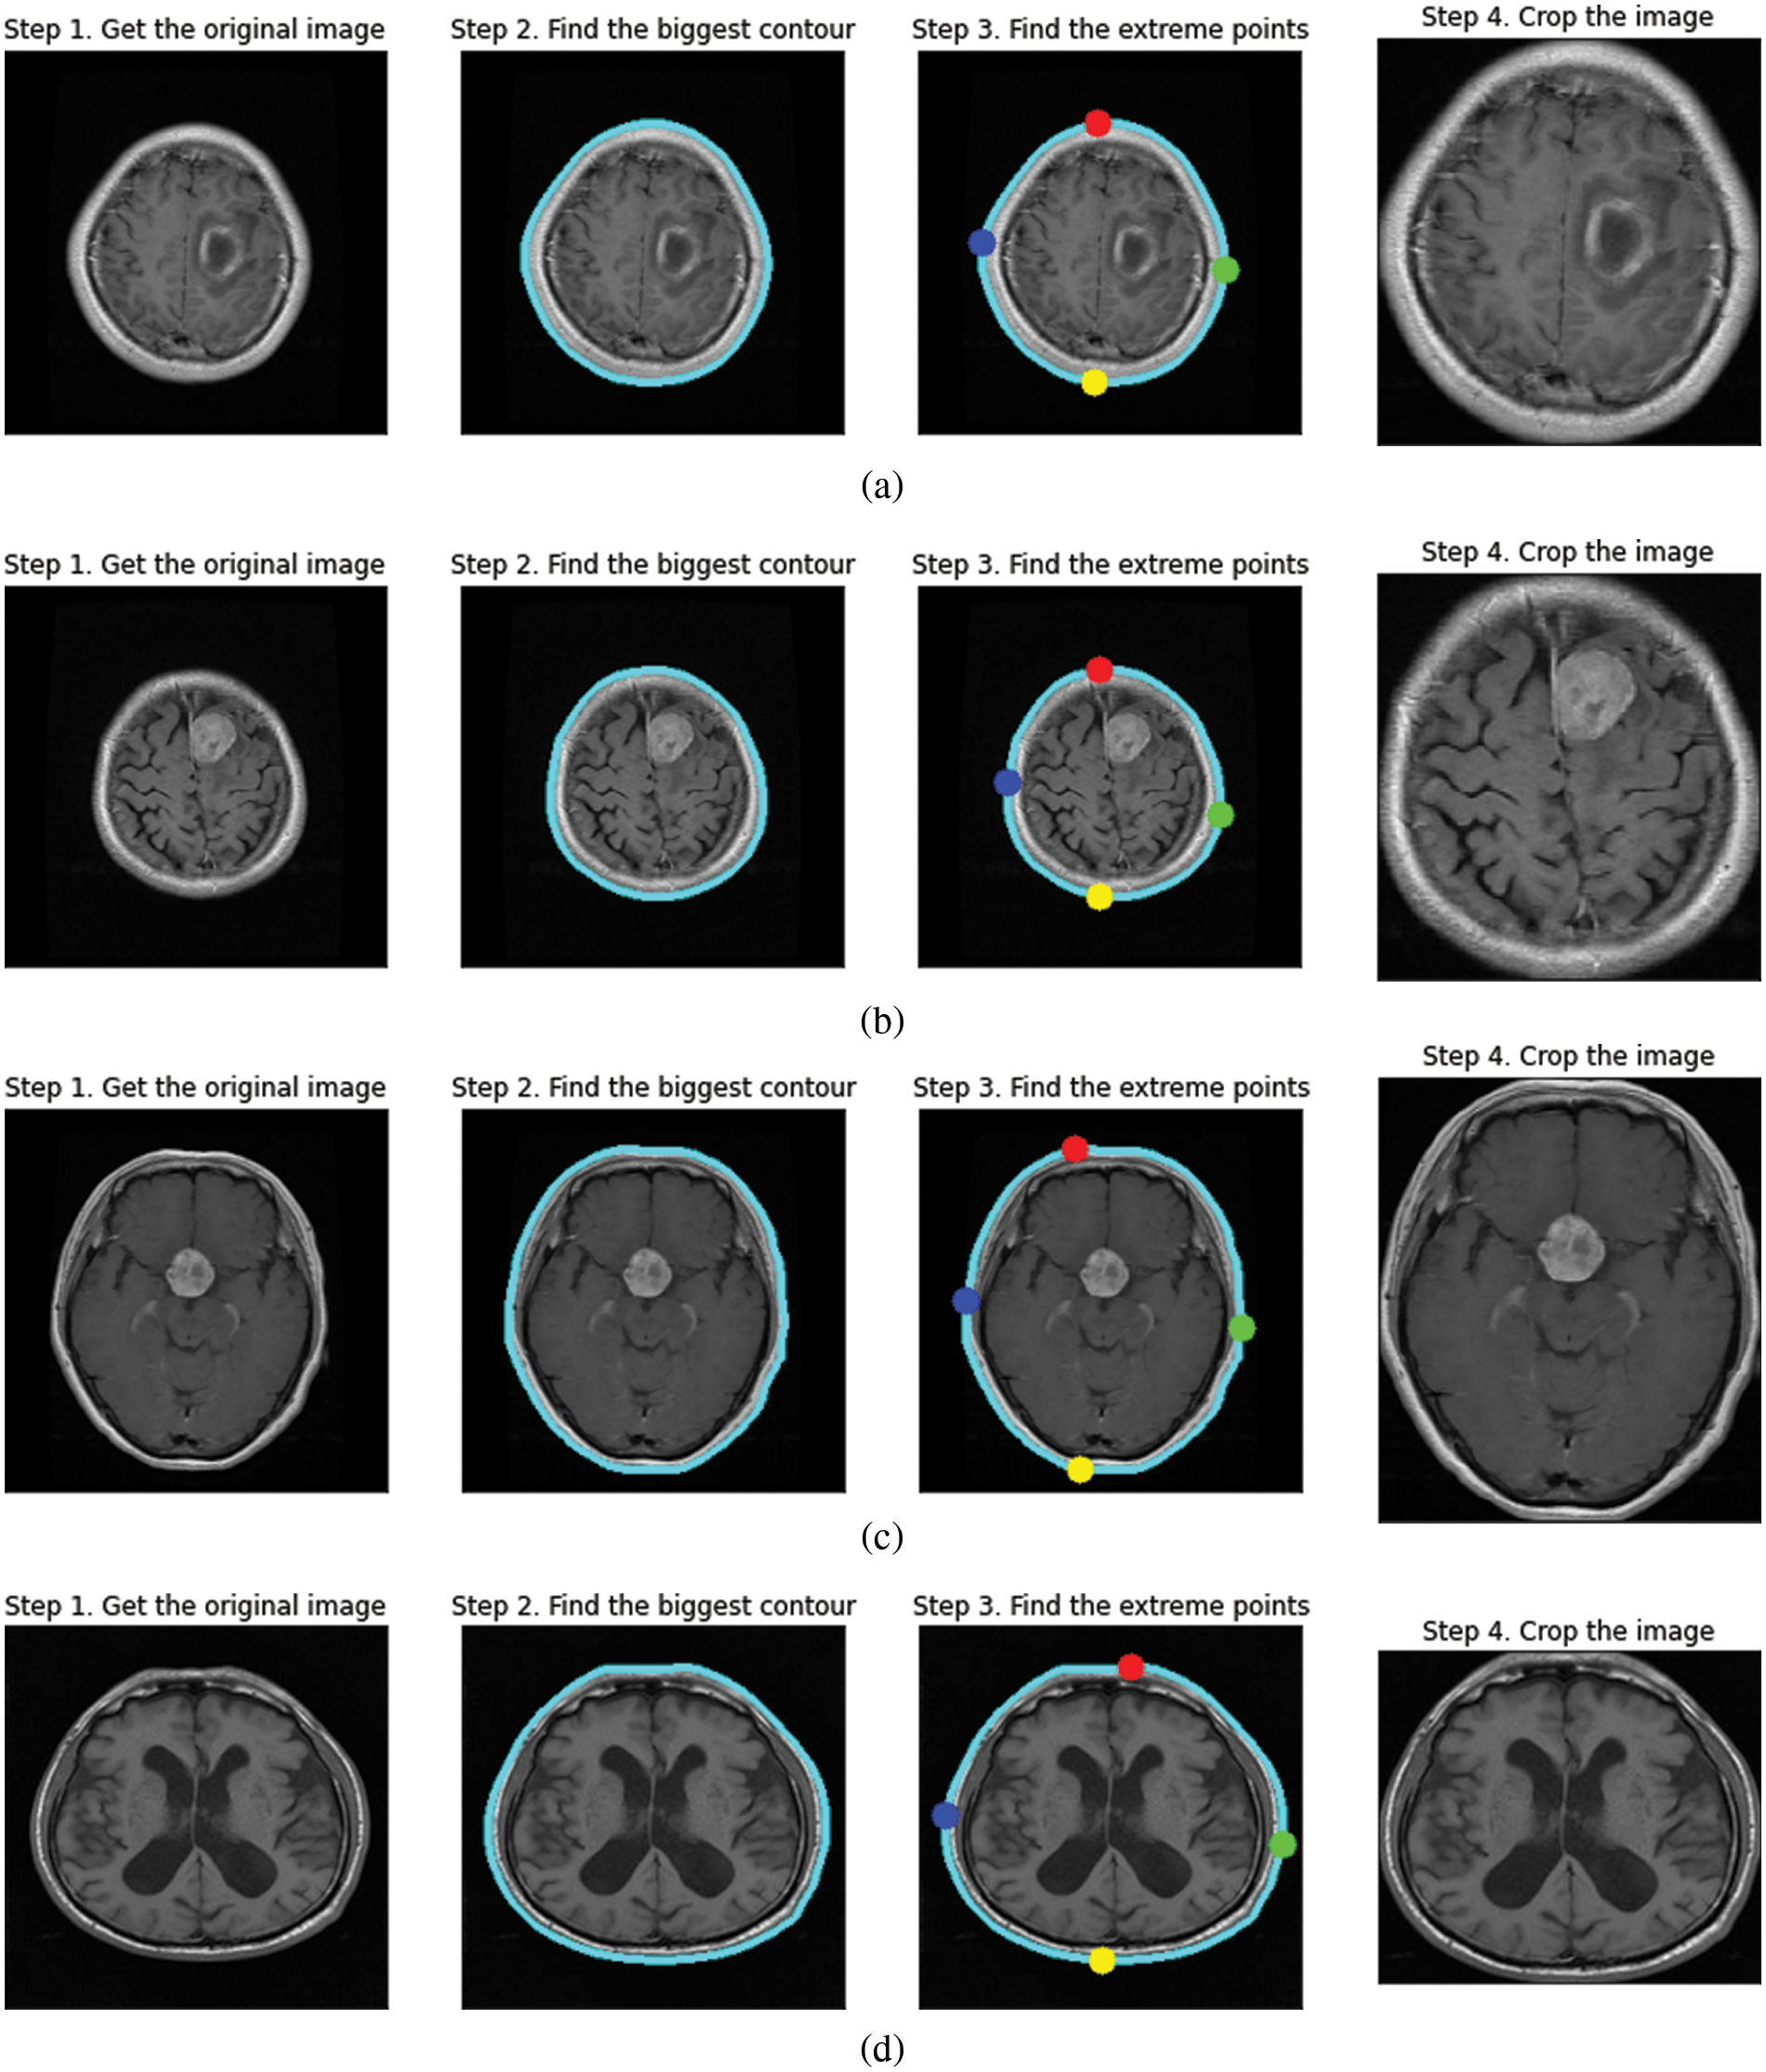

The steps for image preprocessing are defined in the following manner, and the preprocessed image outputs at every stage have been explained in Fig. 4.

Figure 4: Contour extraction outputs for (a) glioma tumor (b) meningioma tumor (c) pituitary tumor (d) no tumor

i) Contour is the edge boundary. To find the contours of the inputted MRI image, we call “cv2.findContours”, which is followed by sorting the contours to find the biggest one, the resultant biggest contour of brain matter is stored as a NumPy array of (x, y) coordinates.

ii) After extracting the contour as a Numpy array, we plot the extreme points in the four directions labeled Red-North, Blue-West, Green-East, and Yellow-South. The largest and smallest x-coordinate in the NumPy array results in “West” and “East” values, respectively, similarly the largest and smallest y-coordinate in the NumPy array results in “North” and “South” values, respectively.

iii) After plotting, the image is cropped concerning the extreme points.

Contour Extraction helps in zooming into the brain region removing the background. It helps the model to get a uniform aspect ratio of the object, that is the brain and prevents the convolution neural network to train weights specifically for zooming in or out from the image. Furthermore, it reduces the loss of information when converting to a smaller size as required in the input shape.